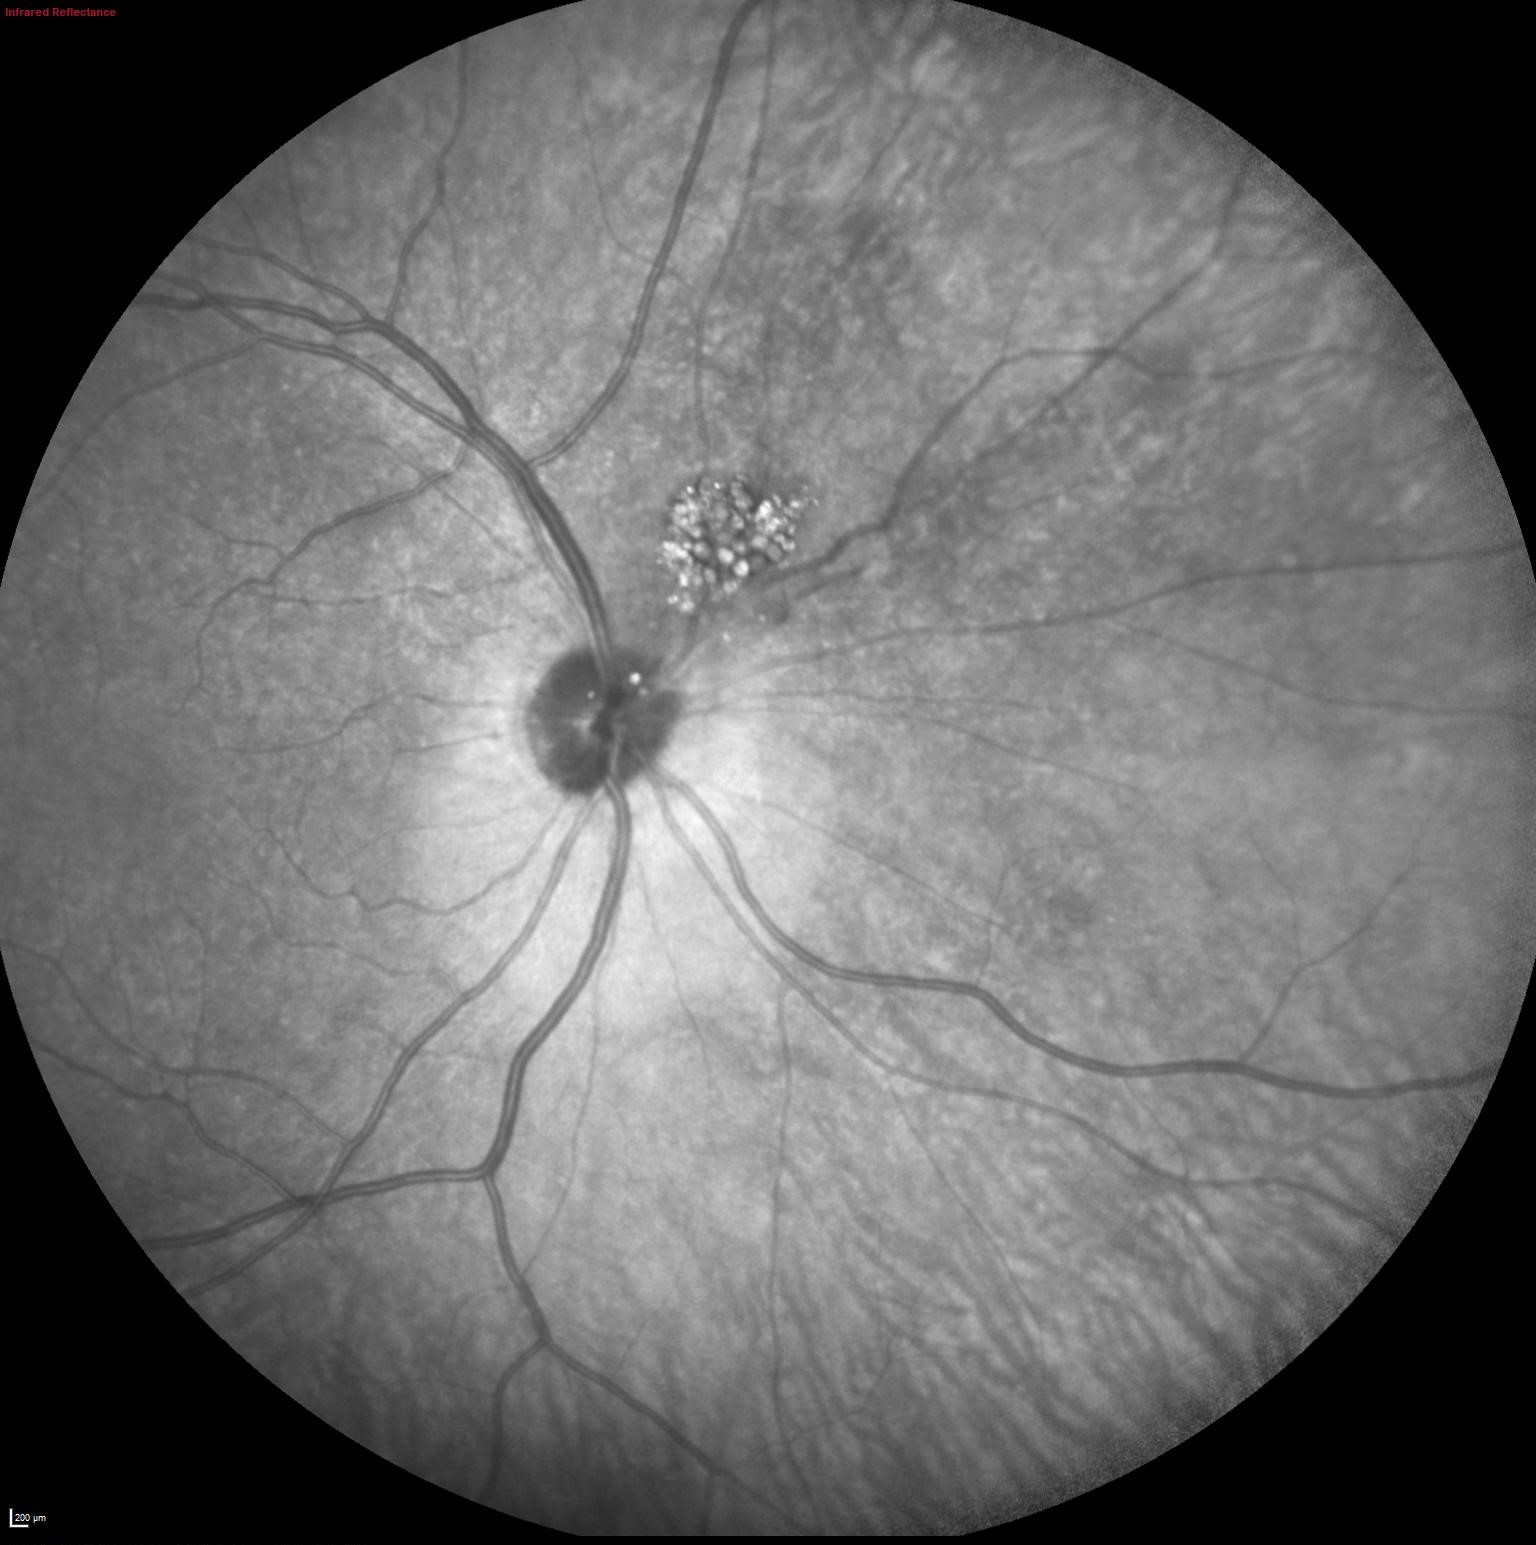

Infrarrojo